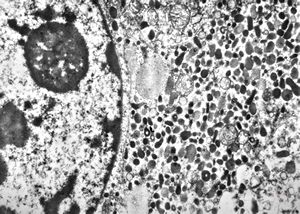

M, 63y. | suprarenal neuroblastoma

M, 3y. | suprarenal neuroblastoma